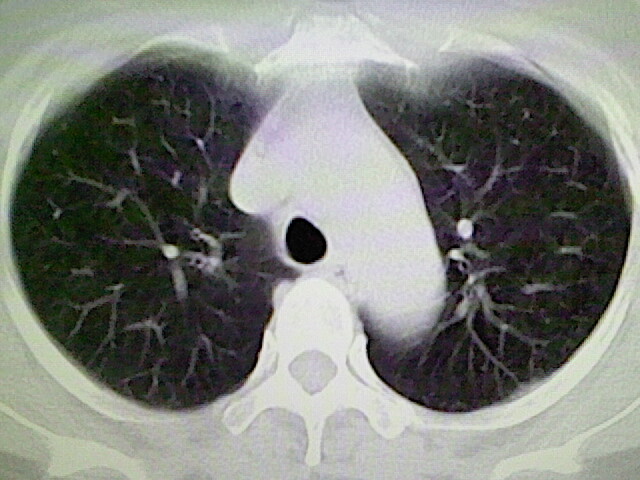

女,52岁,咳嗽,咳痰多日

左下肺陈旧纤维索条!

左肺舌段炎性改变

我见过几例,为炎症后纤维条索

慢性炎症后改变

考虑慢性炎性病灶粘连牵拉改变。

左肺舌叶纤维锁条病变。

左肺上叶下舌段炎症并局部胸膜反应。

左肺舌叶纤维索条影。

左肺舌叶段陈旧性病变

左肺舌段炎性反应。片子的质量太不好了。

左肺舌段炎性

炎性改变

左肺舌叶纤维索条影